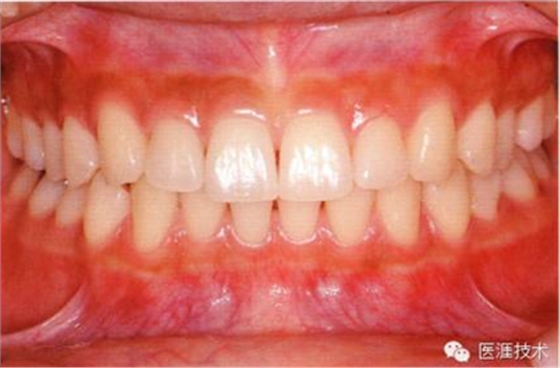

65歲男性的健康口腔內(nèi)部

65歲男性。糖尿病與高血壓病史,目前治療中,40歲左右戒煙。有唾液減少傾向,但目前尚未見對牙齒及牙周組織的影響。初診時齲齒治療后,來院就診保養(yǎng)10年,雖因刷牙過度有牙齦萎縮,但牙齒及牙周組織仍保健康。如可妥善維持菌斑控制,則可維持牙周組織健康,不會減少牙周組織。